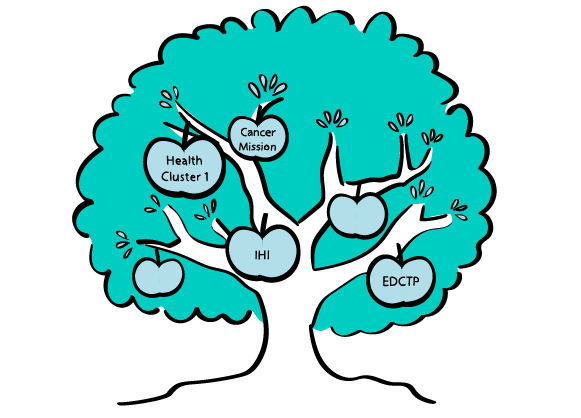

Health Funding Opportunities in Horizon Europe? There are so many!

Health is a priority for all of us and European funding for health research is crucial for tackling major public health challenges. Horizon Europe Cluster 1 Health provides essential resources to address EU health priorities and ensure a healthier future. The draft Work Programme for 2025 is already online, offering researchers and innovators the opportunity to plan and form consortia for successful submissions to the deadline in September 2025.

The official call will be published in May, with an info day and brokerage event hosted by the European Commission and National Contact Points for Health. Topics for 2025 include intellectual disabilities, health impact of pollution, microplastics, mental health, infectious diseases, AI in healthcare and biomedical research, and medical devices. Early preparation will give you a competitive edge. Join one of our info events in the coming weeks. The 2026-2027 Work Programme is also in development and will launch at the end of 2025.

Two other important EU funding opportunities among many in the field of health include:

The European and Developing Countries Clinical Trials Partnership (EDCTP), with a total budget of €1.86 billion (2021-2027), funds clinical research, research capacity development, and networking to accelerate the development of effective, safe, accessible, affordable, and digital medical interventions for poverty-related infectious diseases affecting sub-Saharan Africa. The EDCTP also funds overarching topics such as the effect of climate change on these diseases. The next call is expected in late 2025.

The Innovative Health Initiative (IHI) offers total funding of €2.4 billion (2021-2027) to improve healthcare quality and patient safety, in collaboration with industry stakeholders. IHI calls cover topics from pharmaceuticals and biotechnology to medical technology and big data. Projects focus, for example, on the discovery, development and testing of new molecules and mechanisms of action or on the development of methodologies for the assessment of safety and health outcomes. New calls are planned soon.